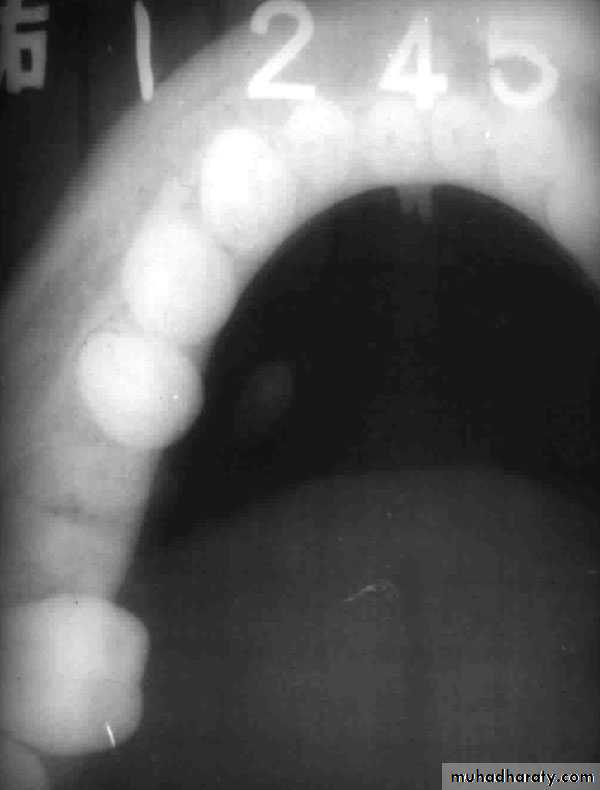

Submandibular Gland - Sialolithiasis

Diagnosis

Pain and sudden enlargement of gland while eating

Palpation of stone in the submandibular duct

Occlusal radiograph (80%)

Sialogram